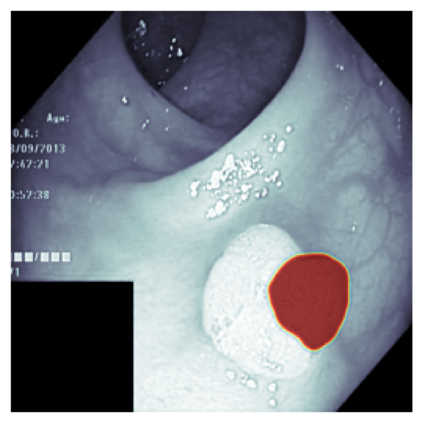

The sigmoid activation is the standard output activation function in binary classification and segmentation with neural networks. Still, there exist a variety of other potential output activation functions, which may lead to improved results in medical image segmentation. In this work, we consider how the asymptotic behavior of different output activation and loss functions affects the prediction probabilities and the corresponding segmentation errors. For cross entropy, we show that a faster rate of change of the activation function correlates with better predictions, while a slower rate of change can improve the calibration of probabilities. For dice loss, we found that the arctangent activation function is superior to the sigmoid function. Furthermore, we provide a test space for arbitrary output activation functions in the area of medical image segmentation. We tested seven activation functions in combination with three loss functions on four different medical image segmentation tasks to provide a classification of which function is best suited in this application scenario.